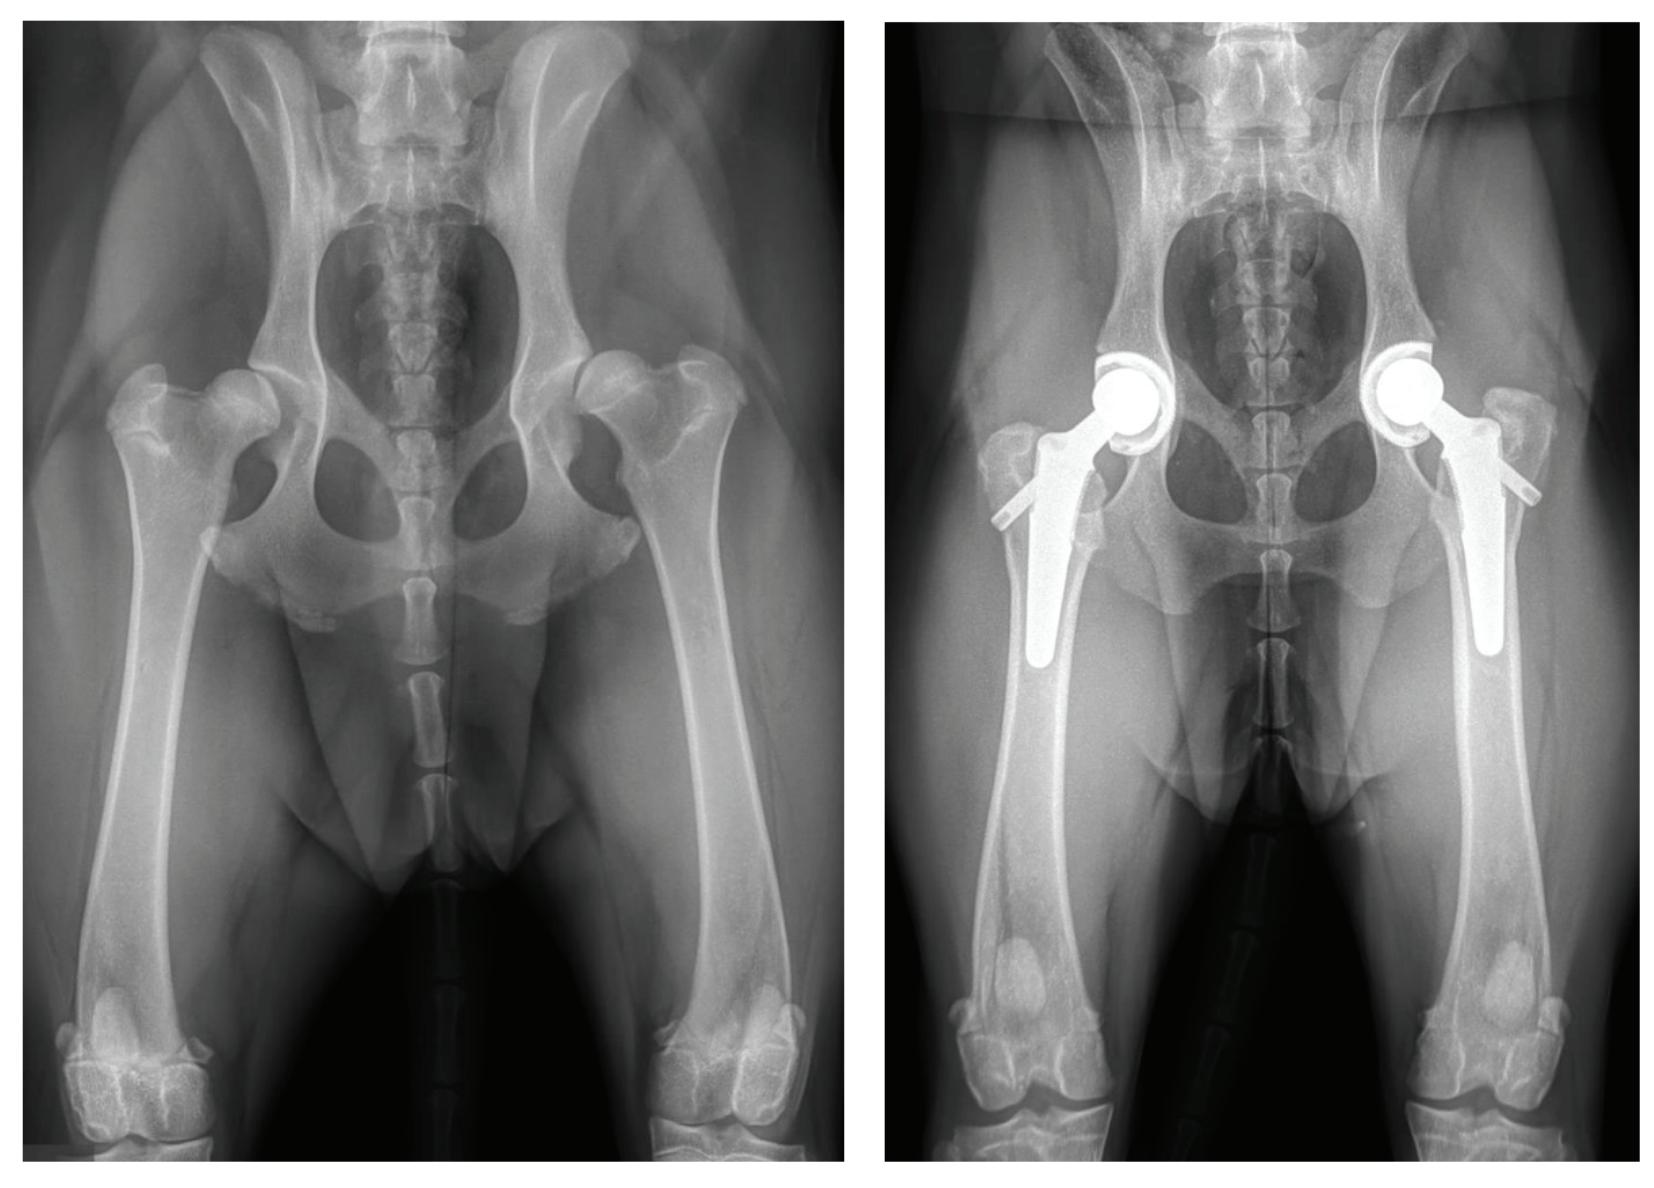

by Meghan Sullivan, DVM, DACVS Portland Veterinary Emergency and Specialty Care

ip dysplasia is the most common canine orthopedic condition. Despite the fact that is used as a âcatchallâ lameness phrase, it is a specific condition. It results in laxity (looseness) of the hip joint which consists of a ball (femoral head) and socket (acetabulum) joint. The femoral head can rub on the acetabulum which results in a shallow acetabulum and flattening of the femoral head. The sequela is pain, erosion of bone, loss of cartilage, swelling, and arthritis. It is most commonly found in large and giant breed dogs, though it can be seen in any breed. Just imagine the discomfort of âbone on boneâ pain!

Symptoms of hip dysplasia usually present in two groups. Young dogs may have significant hip laxity but not yet have arthritis. They present with lameness in the hind end, bunny hopping, reluctance to exercise or jump, and pain on palpation of the hips. Older dogs have developed secondary hip arthritis due to the hip dysplasia. They usually show pain secondary to joint remodeling, loss of range of motion and the pain of arthritis. They can have chronic lameness, stiffened hind end, trouble walking or jumping, muscle atrophy and do not resolve despite medications. Symptoms can be intermittent at first, and typically worsen after âweekend warriorâ activities. Remember that our âbest friendsâ hide pain very well, so be vigilant for even subtle symptoms.

Hip dysplasia is diagnosed on physical exam and with radiographs. Commonly, affected dogs have a wide or narrow-

based stance, âbunny hopping gaitâ and decreased muscle mass in the hind legs. They are painful manipulation of the hip joints and have decreased extension. An Ortolani is a physical test performed to examine for laxity of the joint. Radiographs (xrays) can confirm laxity, subluxation or luxation, arthritis, and muscle atrophy. Sedation is typically utilized to relax the patient and reduce pain so that the proper xray views can be evaluated. In breeds considered high risk, you may consider obtaining a survey xray hip when your dog is anesthetized for spay or neuter surgery.

In a previous article, we have described medical management of hip dysplasia and arthritis. But did you know that total hip replacement (THR) is a surgical option for dogs? It involves the replacement of the diseased acetabulum and femoral head with implants just as is performed in humans. This eliminates the pain by making a normal functional hip joint with no âbone on boneâ pain and improved motion. The implants are titanium and polyethylene and fixed in place with cement, metal bolts, or âpress-fitâ (bone ingrowth) methods. There are several types of total hip replacements performed in dogs but Biomedtrix with either cemented (CFX) press bit biologic (BFX) or hybrid (combination of the two) are the most commonly performed.

The most common indication for a total hip replacement is osteoarthritis secondary to hip dysplasia in a mature dog, or laxity/pain and lameness from hip dysplasia in a young dog. Other reasons for performing a total hip replacement include a hip luxation which could be traumatic or chronic, and certain femoral head fractures which may not be fixable. Total hip replacements are most often performed

in medium, large, and giant breed dogs older than 9 months. However, they can be performed in all sizes of dogs and even cats.

The outcome of a THR is excellent and restores dogs who have chronic lameness and pain to near-normal or normal function. THR dogs immediately bear weight postop on the surgical leg because they are in less pain. By two weeks postop, most dogs are to 90% of their normal function and studies have shown that dogs can return to improved activity as soon as 3 months postop. Radiographs to recheck healing are performed 6-12 weeks postoperatively. They are on leash only during that time and owners use a sling or harness when walking their pet to help prevent slipping/falling. If a pet needs both hips performed, the second side can be performed as soon as 6 weeks after the first. Clients are generally extremely pleased with their dogâs return to full life activities!

All dogs with hip dysplasia should be kept at very lean bodyweight for life. This alone, greatly enhances their movement, function, and activity. A severely overweight patient may not be accepted for a THR surgery due to a potential increased complication rate or make for a more challenging recovery. It is preferable to have dogs (especially young ones) that are symptomatic from hip dysplasia evaluated in a timely manner if medical management has not been successful. A consultation with a surgical specialist can provide further information and options for long term treatment or THR surgery. Our goal with THR is to have our patients back to running, jumping, playing, and doing any physical exercise that they would like to do. Total hip replacement provides the most normal, pain free quality of life and best joint functionality of any of the treatments for hip dysplasia.